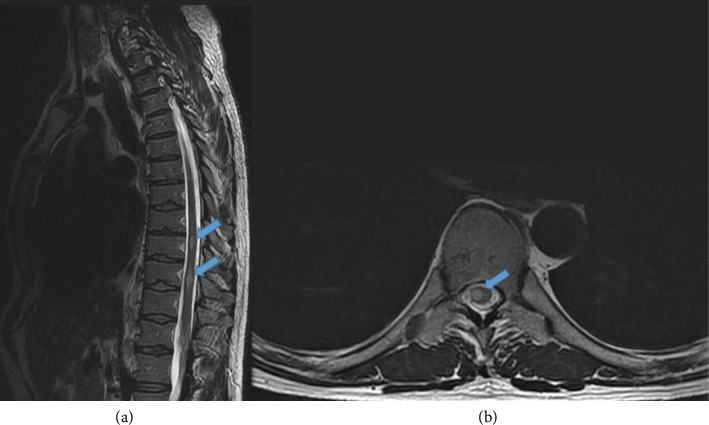

前言:结核治疗期间的矛盾反应的特点是先前存在的结核病变的临床或放射学恶化,或在适当的TBC治疗后出现新的表现。识别这种现象是至关重要的,因为它可能被误认为是治疗失败或复发。尽管在免疫重建炎症综合征后的HIV患者中有广泛的报道,但关于HIV阴性患者的文献很少。病例系列:我们报告了三例免疫功能正常的中枢神经系统结核(CNS-TBC)患者,他们在适当的TBC治疗后出现了矛盾反应。这些包括不同的临床和放射表现,如持续性头痛、结核瘤的出现或进展、脑梗死和脊髓炎。从抗tbc治疗开始平均2.5个月内发生矛盾反应。结论:我们的研究结果强调了密切监测抗tbc治疗后患者的重要性,以迅速发现潜在的并发症。在进行彻底的鉴别诊断时,应考虑到对结核分枝杆菌复合体抗原的过度免疫反应引起的矛盾反应,包括其他中枢神经系统感染、肉芽肿或肿瘤疾病、治疗失败或治疗相关毒性。在这种情况下,确保充分坚持抗tbc治疗和免疫抑制剂至关重要。

Introduction: Paradoxical reactions during tuberculosis (TBC) therapy are characterized by clinical or radiological worsening of preexisting tuberculous lesions or the appearance of new manifestations following appropriate TBC treatment. Identifying this phenomenon is crucial, since it can be mistaken with treatment failure or relapse. Although widely described in HIV patients following immune reconstitution inflammatory syndrome, the literature on HIV-negative patients is scarce. Case Series: We present three cases of immunocompetent patients with central nervous system tuberculosis (CNS-TBC) who developed paradoxical reactions following appropriate TBC therapy. These included diverse clinical and radiological manifestations, such as persistent headaches, apparition or progression of tuberculomas, cerebral infarcts, and dorsal myelitis. Paradoxical reactions occurred within an average of 2.5 months from the start of anti-TBC treatment. Conclusion: Our findings underscore the importance of closely monitoring patients following anti-TBC treatment to identify potential complications rapidly. Paradoxical reactions due to exaggerated immune response to Mycobacterium tuberculosis complex antigens should be considered in a thorough differential diagnosis including other CNS infections, granulomatous or neoplastic disorders, treatment failure, or treatment-related toxicities. Ensuring adequate adherence to anti-TBC treatment and immunosuppressants is essential in such cases.